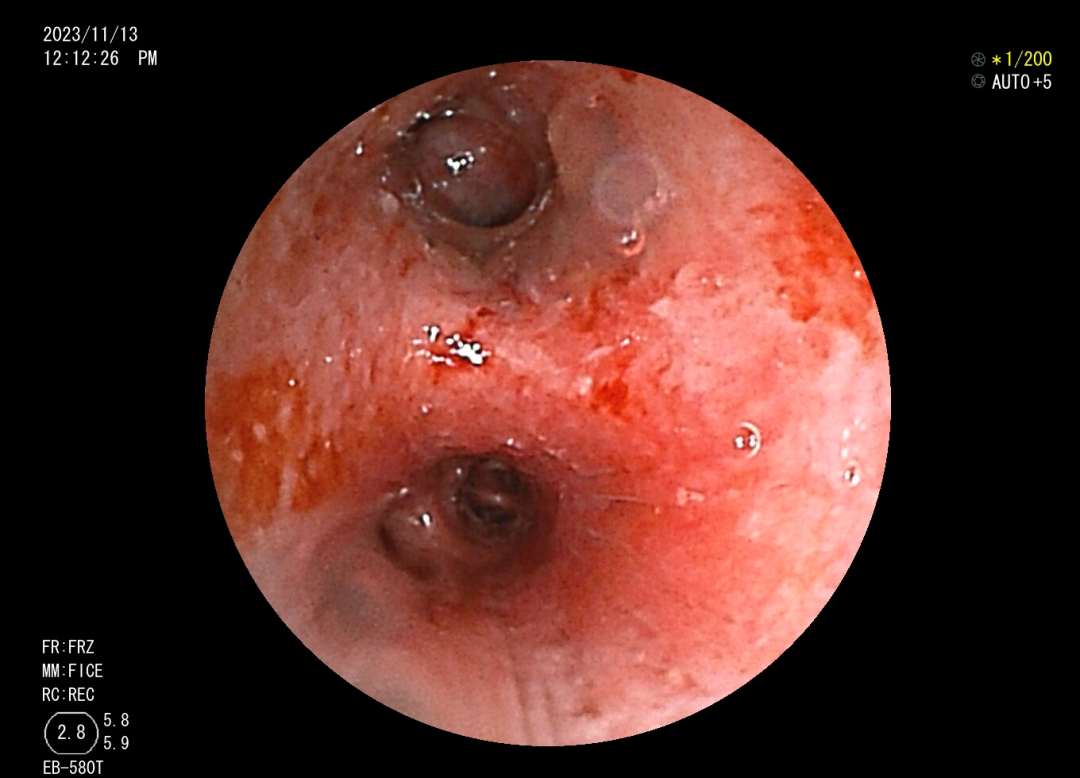

肺科醫(yī)院)住院治療。 10月10日,我院內(nèi)鏡中心為小邰進(jìn)行了第一次支氣管鏡檢查,檢查提示小邰左肺上葉可以看見巨大新生物完全阻塞管腔,充分評(píng)估后,行手術(shù)治療,手術(shù)中應(yīng)用了活檢鉗、異物鉗、冷凍、高頻電刀、內(nèi)鏡下超聲探頭等方法,既保證了患者的安全,又達(dá)到了治療目的,通過三次手術(shù),終于將左上葉巨大腫塊清除掉了。術(shù)后1周復(fù)查胸部CT小邰左肺上葉復(fù)張開來,感覺胸悶、氣促癥狀明顯改善,患者家屬和內(nèi)鏡中心的醫(yī)護(hù)人員由衷為他感到開心。 左上葉巨大新生物阻塞管腔 治療后左上葉恢復(fù)通暢 高頻電消融治療 支氣管結(jié)核科普知識(shí) 在日常生活中大家可能經(jīng)常聽說肺結(jié)核,可是又有多少人知道支氣管結(jié)核呢?其實(shí)支氣管結(jié)核是肺結(jié)核的一種特殊類型,支氣管結(jié)核起病緩慢,癥狀隱匿,缺乏特異性,主要表現(xiàn)為間斷咳嗽、咳痰等。因?yàn)榍捌诎Y狀不重,往往被患者所忽視,等病變逐漸增大,阻塞氣管、支氣管時(shí)可出現(xiàn)嚴(yán)重的呼吸困難、咯血、胸痛等癥狀,嚴(yán)重氣道狹窄甚至可能危及生命。支氣管結(jié)核的診斷需要行支氣管鏡的檢查來發(fā)現(xiàn),早期診斷、早期治療是決定預(yù)后的關(guān)鍵。中晚期出現(xiàn)纖維疤痕狹窄,往往療效不佳。支氣管結(jié)核在發(fā)病4~6個(gè)月內(nèi)支氣管狹窄發(fā)生率可達(dá)68%,隨著時(shí)間延長,并發(fā)癥發(fā)生率還將進(jìn)一步提高。嚴(yán)重的支氣管狹窄和阻塞可引起肺不張、反復(fù)感染、呼吸衰竭和窒息,為死亡的主要原因。故支氣管結(jié)核患者早期進(jìn)行支氣管鏡檢查、介入治療是十分有必要的,可以有效改善病情及預(yù)后,目前我中心內(nèi)鏡下介入治療包括病變支氣管藥物灌注治療、活檢清理、高頻電消融、冷凍切除、狹窄管腔內(nèi)支架置入、球囊擴(kuò)張、超聲支氣管鏡等。 早識(shí)早治,呼吸健康從關(guān)懷開始。通過支氣管鏡介入治療,我們致力于為患者提供最先進(jìn)的手段和關(guān)懷,確保在關(guān)鍵時(shí)刻護(hù)航呼吸健康。讓我們攜手,將關(guān)注和治療延伸至每個(gè)支氣管,為患者帶來更明朗的未來。